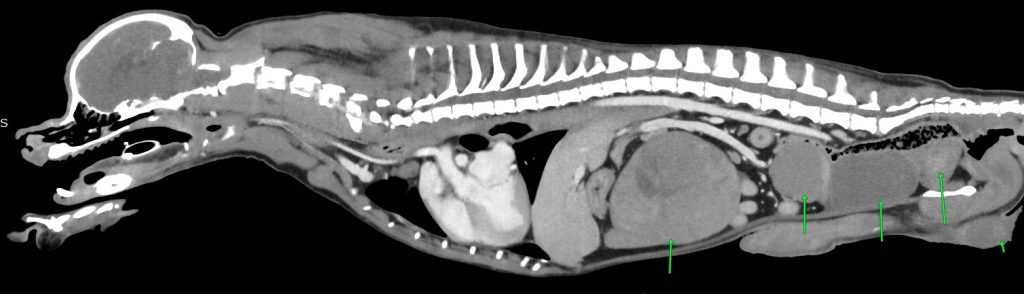

手術の可否を見極めるため、全身麻酔下のCT検査開始(もちろん、オーナー了解済み)

矢印左から脾臓腫瘤、不明な腫瘤、膀胱、前立腺、睾丸

チワワの体にしては大きすぎる腫瘍が2つ

左右の睾丸に腫瘍が数個